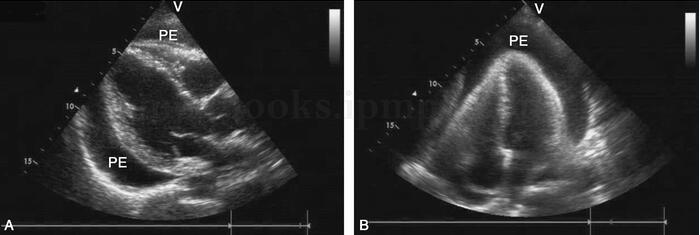

图2‐1‐220 中‐大量心包积液

A﹒左室长轴切面;B﹒心尖四腔心切面;PE:心包积液

超声描述 心脏各房室腔内径正常。升主动脉及主肺动脉内径正常。左室壁厚度正常,静息状态下未见节段性室壁运动异常,左室整体收缩功能正常。各瓣膜形态结构及启闭正常。心包腔内可见中~大量液性暗区。下腔静脉略增宽,塌陷指数略减低。各瓣膜血流频谱速度随呼吸变化幅度略有改变。

超声诊断 中~大量心包积液;下腔静脉略增宽,塌陷指数略减低。